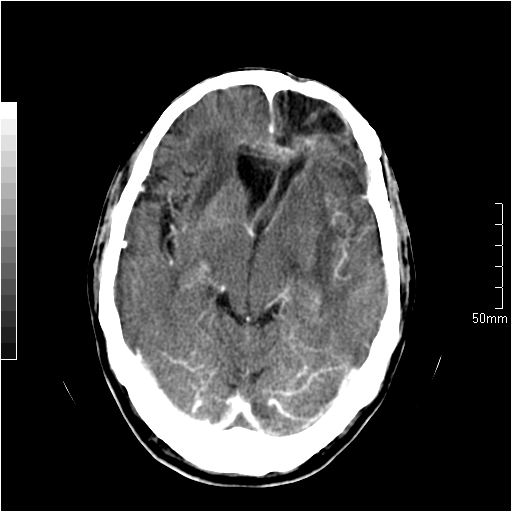

以下是引用天南地北在2007-6-25 12:39:00的发言:[br]有占位效应[br]支持术后复发

以下是引用zjzjr在2007-6-25 12:38:00的发言:[br]左侧复发,右侧转移。